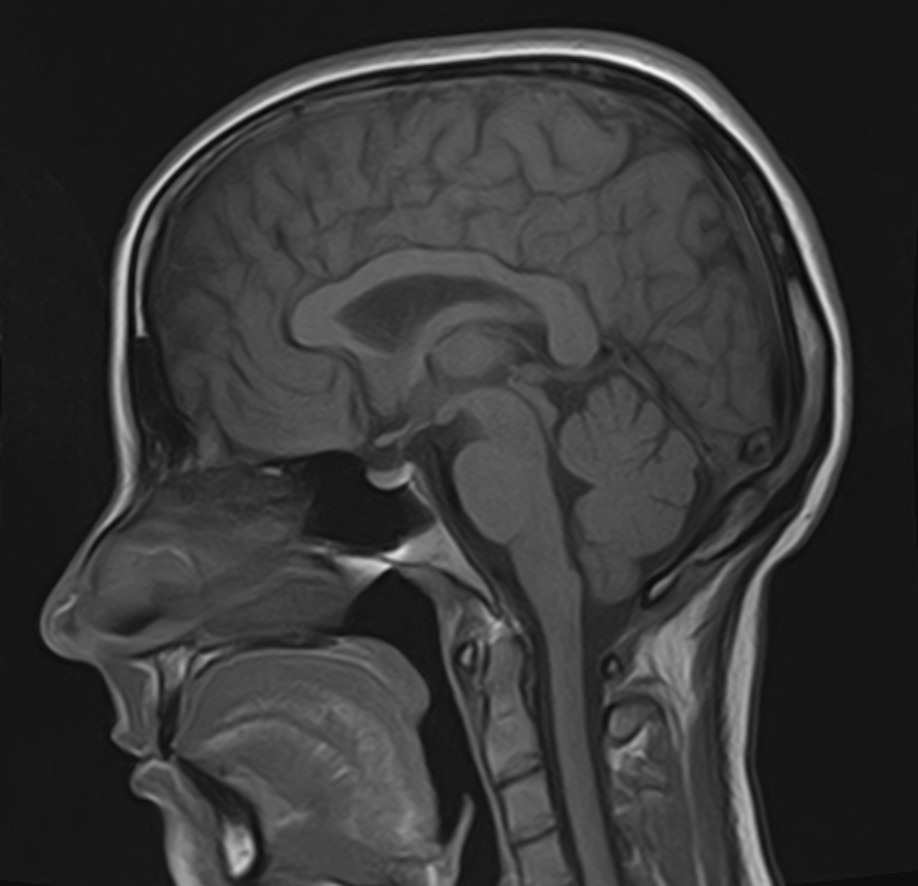

В клинике «Доступная медицина» можно пройти комплексное обследование, включающее в себя несколько протоколов сканирования близко расположенных друг от друга анатомических областей – шейного отдела позвоночника и головного мозга. Метод комплексного обследования оценивает состояние всех структур головного мозга и шейного отдела позвоночника. При этом дополнительные протоколы обследования позволяют визуализировать крупные сосуды шеи и сосудистую сеть головного мозга.

Шейный отдел позвоночника — это самый подвижный сегмент позвоночного столба, который испытывает повышенные нагрузки, подвержен травмам и развитию различных заболеваний. В эту анатомическую область входит 7 верхних позвонков, спинной мозг с отходящими от него нервными корешками.

Кроме того, в области шеи проходят крупные кровеносные сосуды, кровоснабжающие все структуры головного мозга и мягких тканей головы. К ним относятся плечеголовной ствол, сонные и позвоночные артерии, которые далее в полости черепа соединяются между собой в Виллизиев круг. Это анатомическое образование позволяет компенсировать мозговой кровоток при патологических состояниях.

Сканирование проводится на современном высокопольном магнитно-резонансном томографе закрытого типа TOSHIBA VANTAGE TITAN 1,5 Тесла. Магнитно-резонансный томограф производит послойное сканирование исследуемой зоны в разных плоскостях, затем при помощи компьютерных программ преобразует полученные данные в трехмерные изображения. При этом кровеносная система реконструируется как вместе с окружающими тканями, так и отдельно без них.

Что показывает МРТ головного мозга + МРТ шейного отдела позвоночника + МР-ангиография шеи и головного мозга

В рамках проведения данного комплексного исследования можно выявить:

• остеохондроз, спондилоартроз, спондилез, межпозвонковые грыжи, унковертебральный артроз, сколиоз, усиленный или выпрямленный лордоз как нарушение статической функции позвоночника, травмы, аномалии позвоночника.